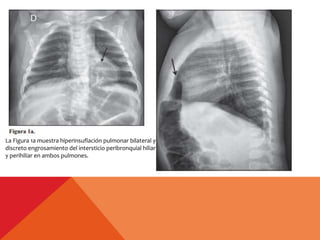

La Figura 1a muestra hiperinsuflación pulmonar bilateral y

discreto engrosamiento del intersticio peribronquial hiliar

y perihiliar en ambos pulmones.

La Figura 1amuestra hiperinsuflación pulmonar bilateral y discreto engrosamiento del intersticio peribronquial hiliar y perihiliar en ambos pulmones.